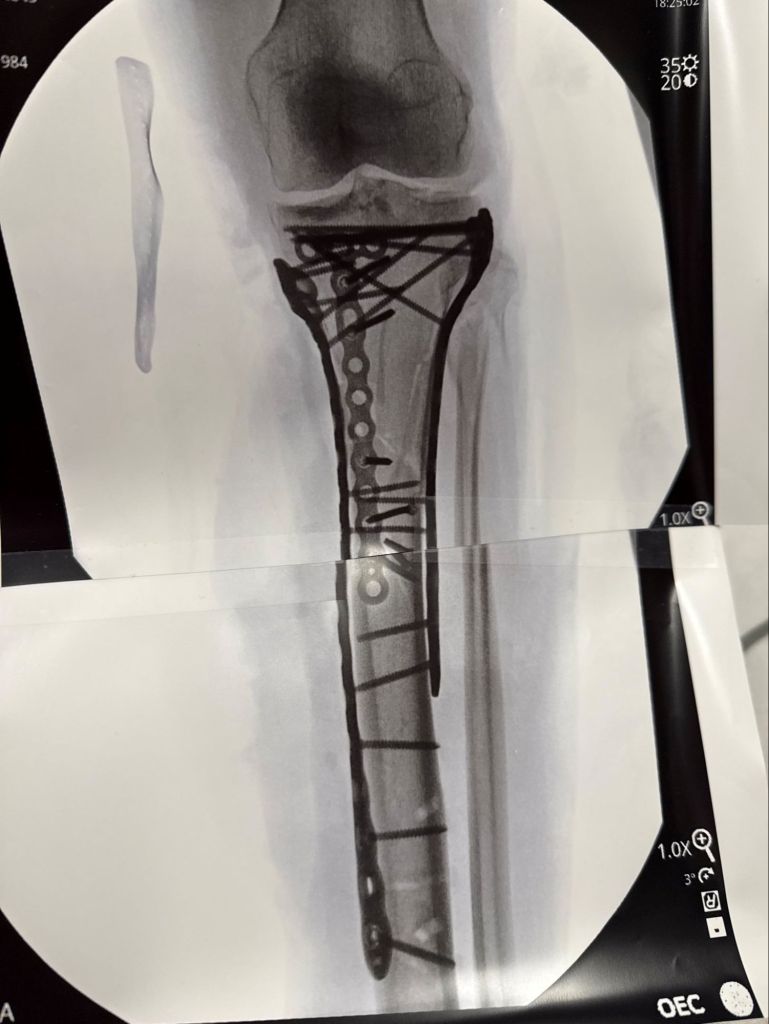

Olympic skier Lindsey Vonn recently shared an x-ray of her broken leg after a crash at the 2026 Winter Olympics. The x-ray displayed her broken bone supported by plates and screws.

Vonn, 41, expressed gratitude to her medical team for their work. She underwent multiple surgeries in Italy after fracturing her left tibia during the Olympic downhill event on February 8.